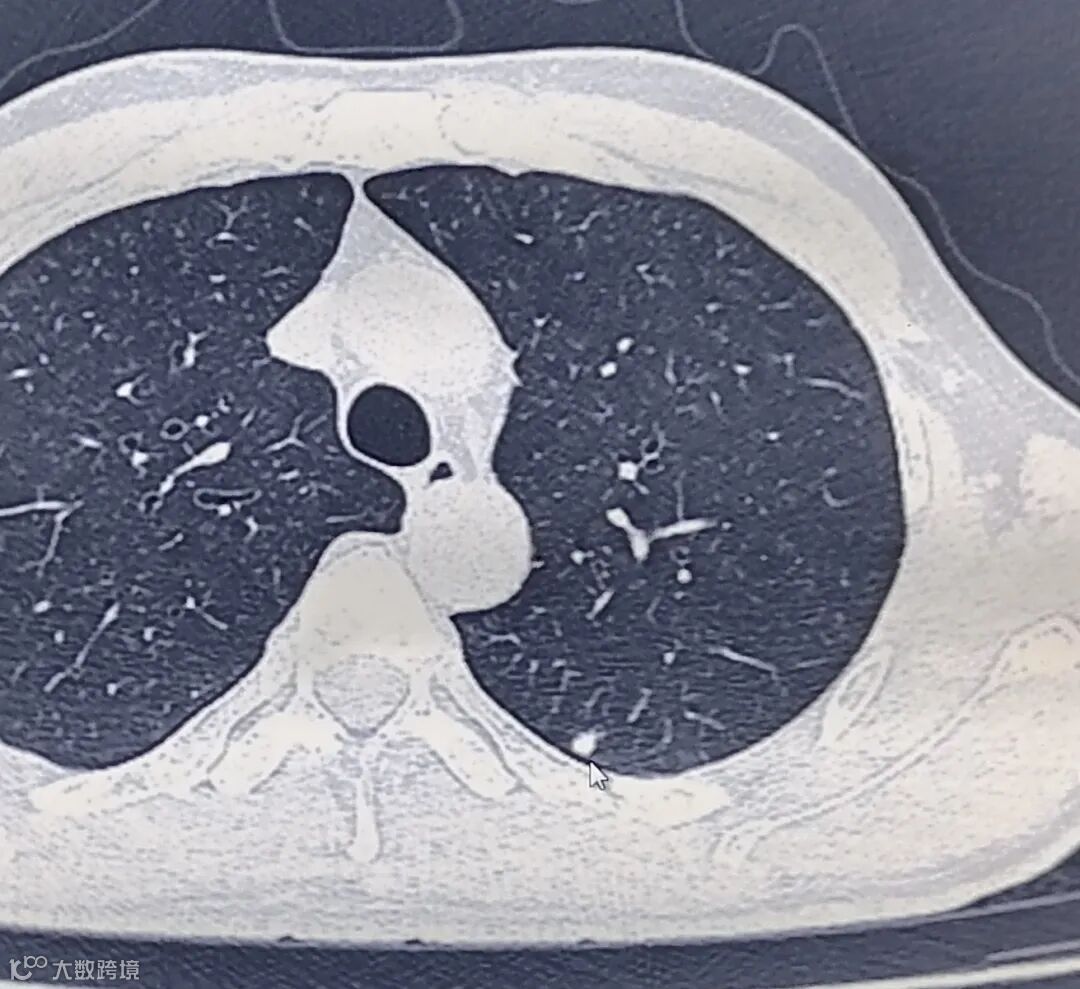

肺结节(pulmonary nodule)是指肺内直径小于或等于3cm的类圆形或不规则形病灶,影像学表现为密度增高的阴影,可单发或多发,边界清晰或不清晰的病灶;小于1cm的被称为肺小结节,而小于5mm的结节称为肺微小结节。

据统计,肺内小结节病变在传统胸部X线中发现率仅为0.2%,而在高分辨力CT中发现率达到40%-60%,文献统计,中国成年人群中肺小结节患有率至少51%,但其中只有约2%-3.6%是恶性病变,大多数为良性病变;但是不论肺小结节的患有率是多少,一个不争的事实是,肺癌是我国发病率第一、死亡率第一的恶性肿瘤,而肺癌的前期大都源自肺小结节。

根据肺内小结节的密度可以分三类: